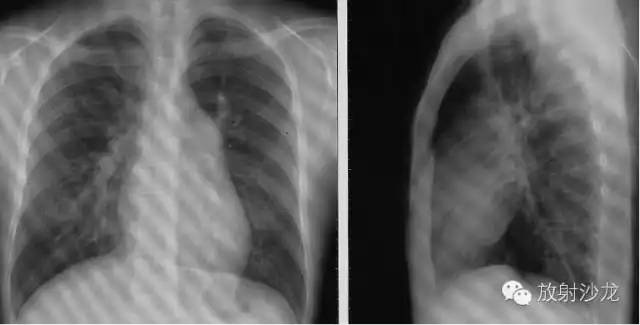

心脏大血管后前位投影 PA View

右心缘:上腔静脉或升主动脉,右房(膈低位右室)。

左心缘:主动脉弓;肺动脉段(心腰)。

左心室:相反搏动点位于肺动脉段与左室间左心耳1 cm。

侧位(Left lateral view),心影从后上向前下倾斜。心前缘: 1.升主动脉;2.右室漏斗部与肺动脉主干;3.右室心后缘;4.左心房;5.左心室。